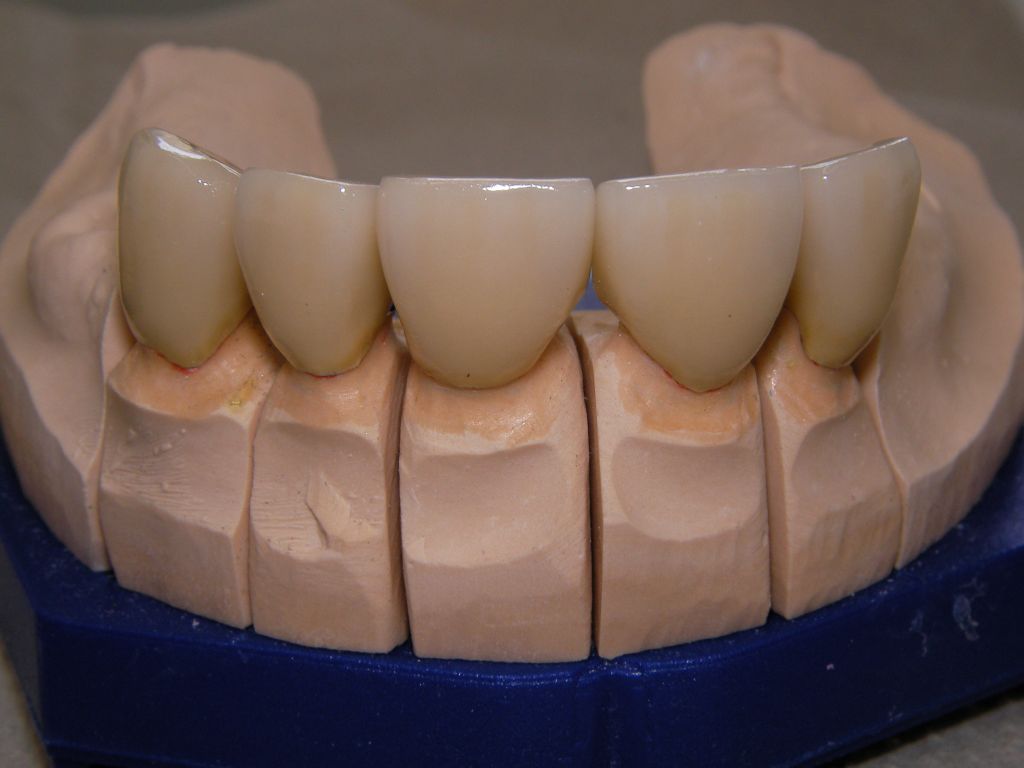

Links das Bild zeigt das Metallgerüst, das später mit Keramik verblendet wurde. Um eine einfache Mundhygiene ebenso wie eine hohe zahntechnische Präzsion zu erreichen, wurden risikobehaftete Verblockungen minimiert. Rechts die Ästhetikeinprobe bei entspannter Oberlippe.

Oberkiefer von vorne

Unterkiefer von vorne

Links Bilder des Oberkiefers, rechts des Unterkiefers. Die Arbeit wurde von dem Dentallabor "Heitmeyer Zahntechnik", Osnabrück, gefertigt. Dem Labor ist hier für die hervorragende Arbeit zu danken, dem Patienten für die Freigabe der Bilder!